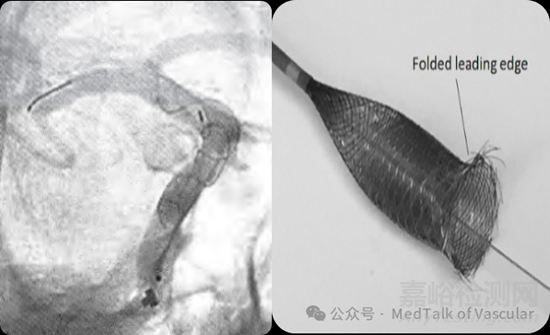

其中血流導(dǎo)向密網(wǎng)支架治療顱內(nèi)動(dòng)脈瘤的原理為:通過(guò)血流導(dǎo)向密網(wǎng)支架的高金屬覆蓋率和高網(wǎng)孔率設(shè)計(jì),對(duì)局部血流進(jìn)行重塑,將載瘤動(dòng)脈向動(dòng)脈瘤內(nèi)的沖擊血流導(dǎo)向遠(yuǎn)端正常血管內(nèi),從而減少局部血流對(duì)動(dòng)脈瘤的沖擊,使動(dòng)脈瘤內(nèi)的血流動(dòng)力學(xué)情況得以改善,最終在動(dòng)脈瘤內(nèi)形成血栓,進(jìn)而實(shí)現(xiàn)動(dòng)脈瘤的閉塞。

圖1,血流導(dǎo)向密網(wǎng)支架治療動(dòng)脈瘤示意圖